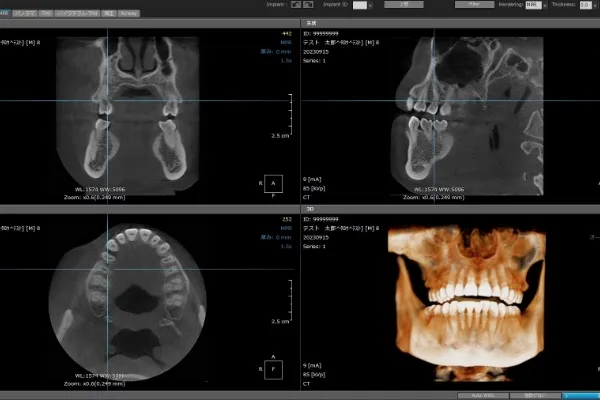

3

CT

X線で口周りの内部を輪切り状にして見ることで、歯の長さや角度、位置などを正確に把握することが可能です。